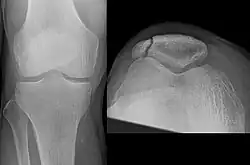

The patella can break in various ways depending on the way it is injured, and into two or more pieces.[1] Types include transverse, the most common, with one fracture line;[5] marginal; osteochondral; and the rare vertical type, or stellate, where a direct compression force gives rise to a comminuted pattern.[5][7] Patella fractures can be further classified as displaced, where the broken ends of bone do not line up correctly and separate by more than 2mm, or undisplaced and stable where pieces of bone remain in contact with each other.[1][7] If fragments of patella bone stick out from the skin it is known as an open patella fracture, and closed if the overlying skin is intact.[1]

-

Transverse fracture of patella -

Comminuted fracture of patella -

Osteochondral fracture of patella -

Vertical patella fracture